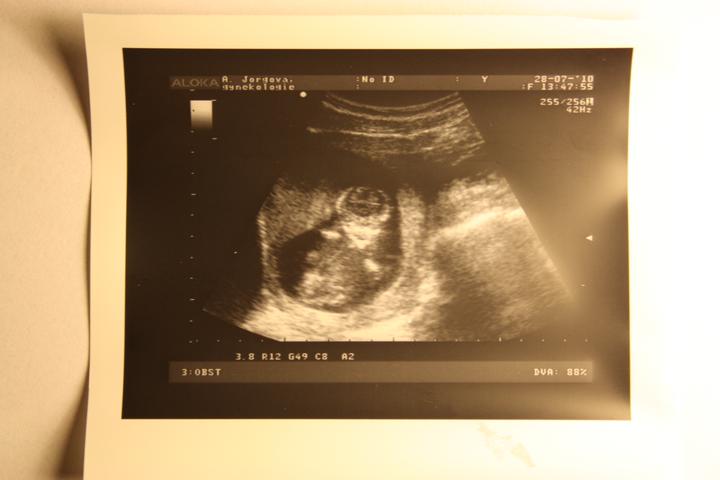

tak srdíčko se dneska krásně třepotalo 🙂